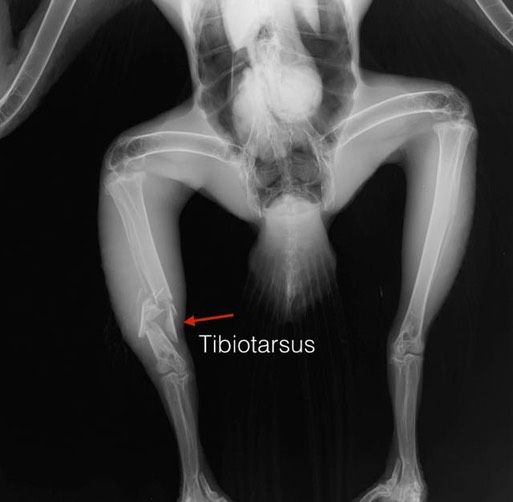

Bald Eagle 18-016

Although overall intakes are down, we have a record three Bald Eagles currently in the clinic. Eagle number three arrived Friday evening from Enterprise, OR. It is likely he crashed into a power line, breaking his right leg and injuring his right elbow. We have immobilized the leg with a splint and hope it can be surgically repaired this week.